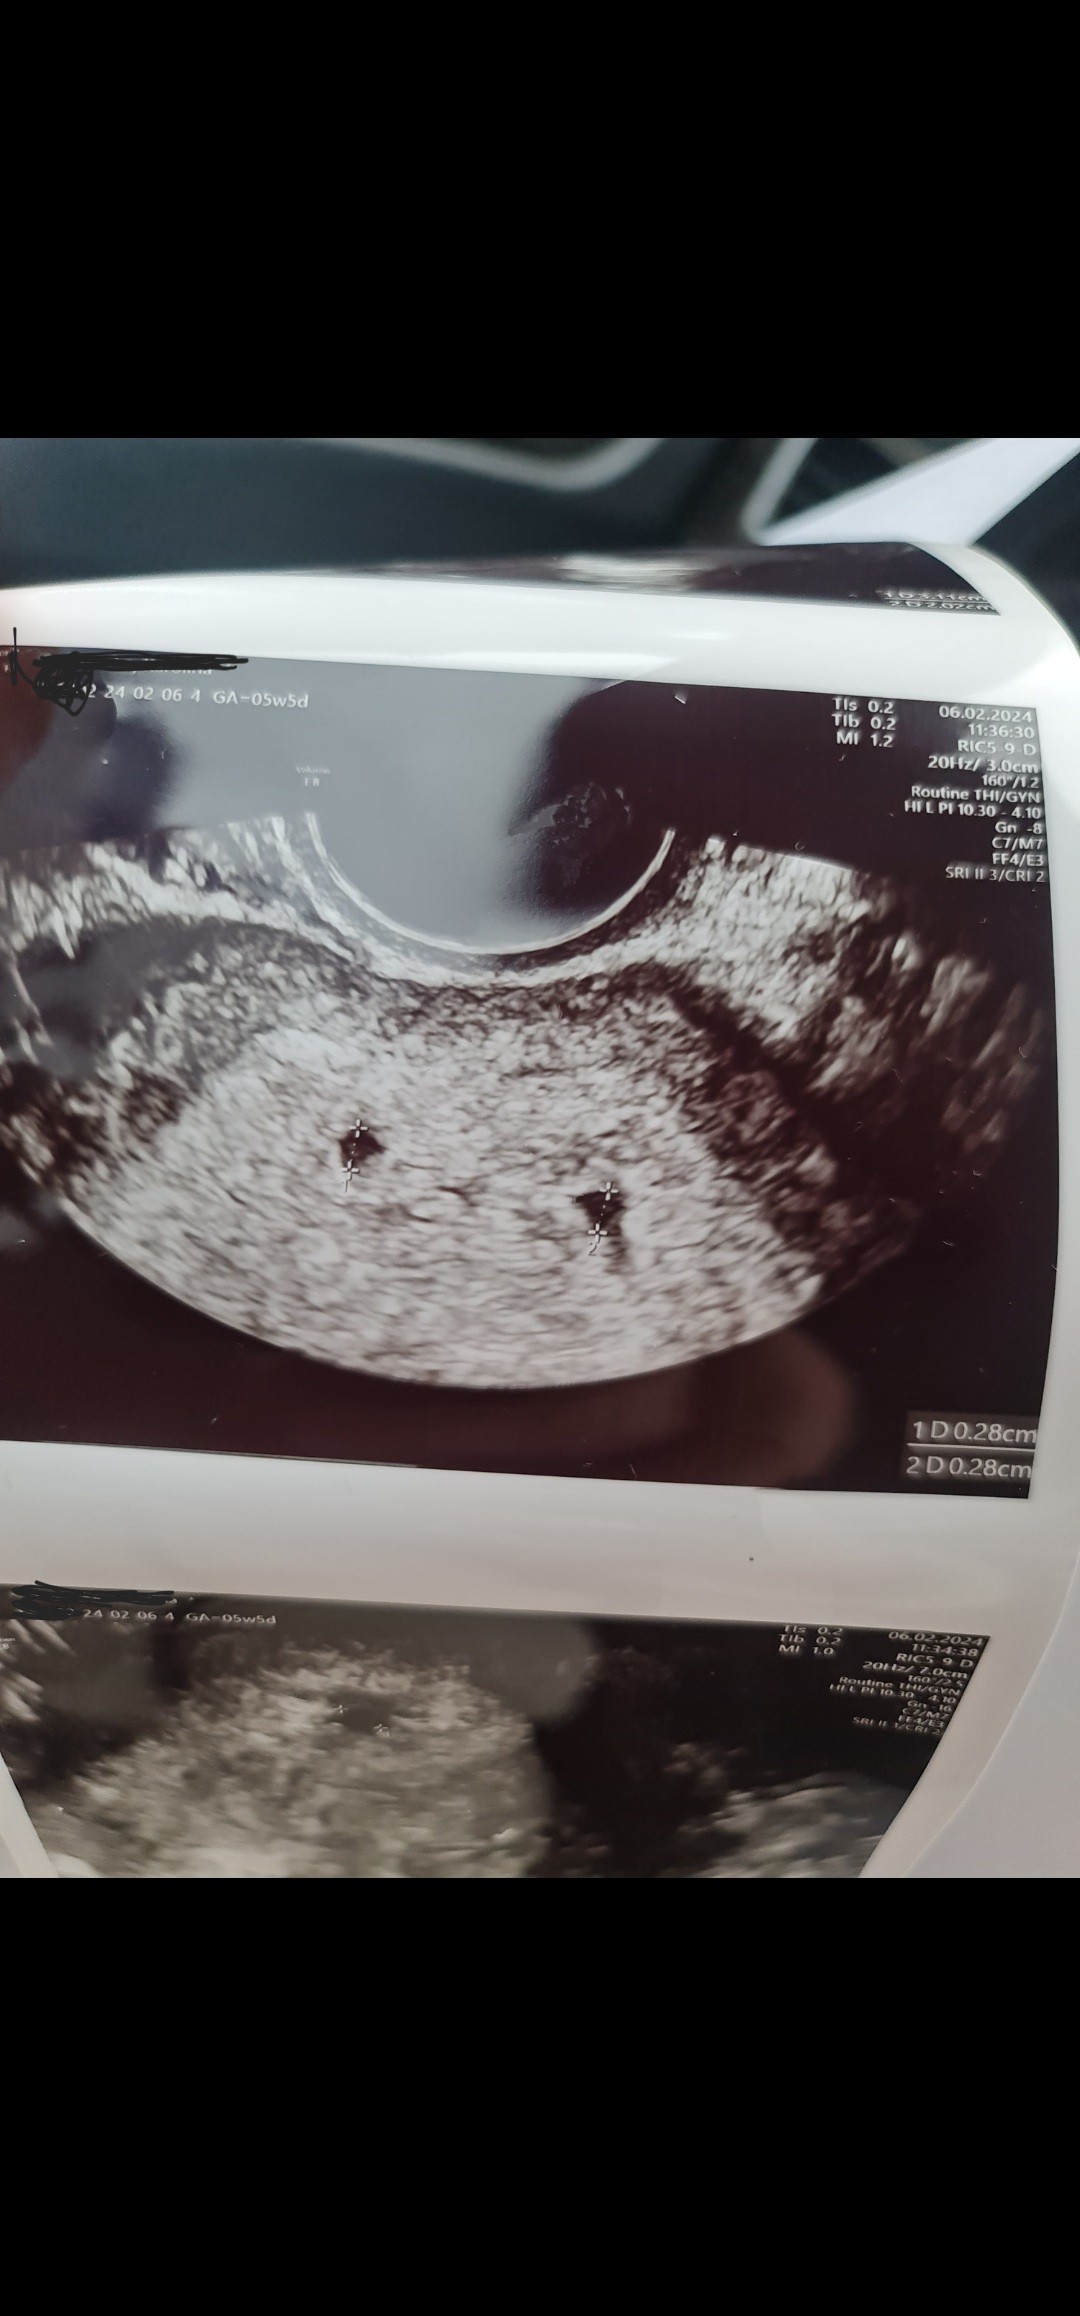

Ciąża bliźniacza?

Witam, wczoraj byłam na pierwszym USG. Najpierw pani doktor nie mogła znaleźć żadnego pęcherzyka a później znalazła jeden a zaraz jeszcze jeden. Czy któraś z Pań mogłaby mi podpowiedzieć czy to faktycznie może być ciąża bliźniacza? Pęcherzyki maja po 2.8 mm, ale nie było jeszcze w żadnym zarodka, za tydzień kolejne badanie ale po prostu nie mogę już się doczekać odpowiedzi na to.